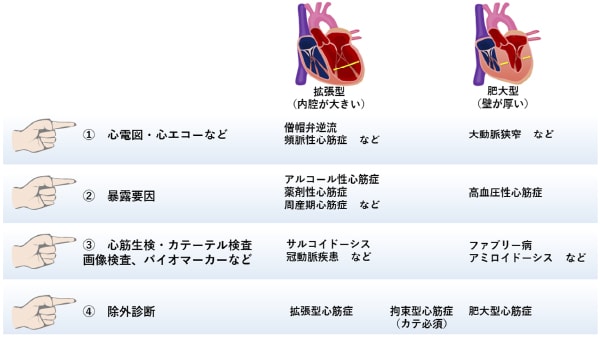

心筋症(cardiomyopathy)は、心拡大(心臓の内腔が大きくなること)や心肥大(心筋が厚くなること)に伴い心臓の収縮能や拡張能が低下して、心不全や不整脈などの合併症を起こす病気です。

心筋症は病態によってアプローチが大きくことなるため、その原疾患の鑑別が必要です。以下に一例として当院で行っている鑑別のステップを示します。

①心電図・心エコーなどの一般的な循環器で行われる検査で“アタリ”をつける

②心機能や心筋の性状に影響する暴露要因を確認する

③ここまで1〜2回の外来診療でできます

④心筋生検・画像検査・カテーテル検査やバイオマーカーなどで二次性心筋症を“rule-in”する:ここでは比較的特殊な診断技術が必要です

⑤残った病態は”rule-out(除外診断)”で原発性心筋症と考える

特異的な治療が有効な二次性心筋症として、心アミロイドーシス、ファブリー病、あるいは心サルコイドーシスなどが挙げられます。